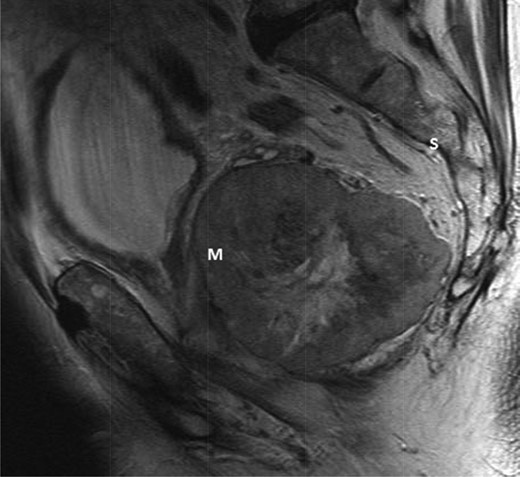

An elderly man in his seventies presented to the Urology department with two episodes of acute urinary retention. There were no rectal symptoms and rectal examination revealed an enlarged prostate. He underwent a laser transurethral resection of prostate during which a large palpable pelvic mass was noted. The subsequent urgent MR pelvis revealed a large tumour in the mesorectum arising from the anterior rectum 10 × 8.5 cm (Figs 1 and 2). A transrectal ultrasound and biopsy were performed; histology revealed a spindle cell tumour, with positive immunostains for CD117 and DOG1 with 5 mitoses per 50 high power fields. This was confirmed to be a locally advanced high-risk GIST.

T2-weighted sagittal image demonstrating a large mass (m) anterior to the sacrum (S) and posterior to the bladder.